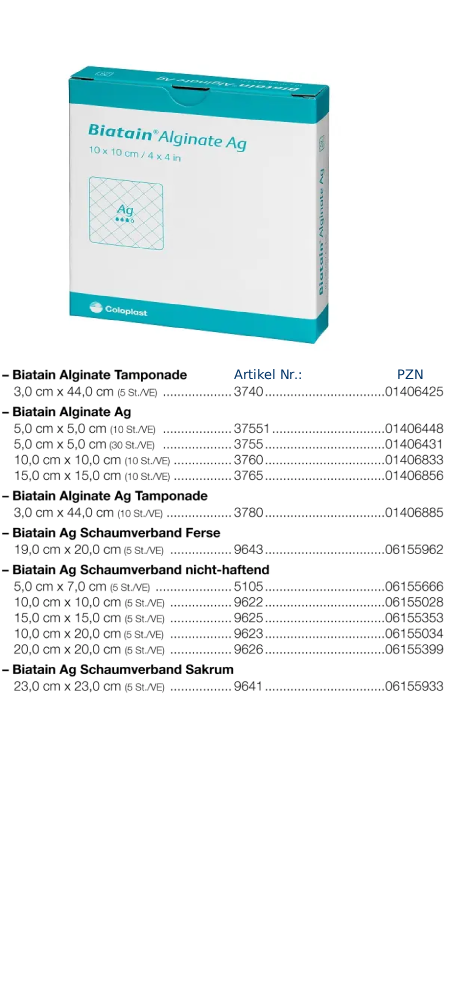

Biatain Alginate Ag

Biatain Alginate Ag Tamponade